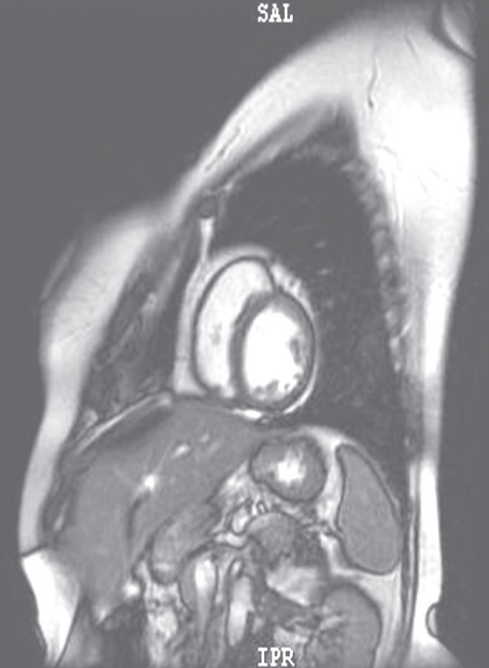

摘要:關于擴張性心肌病的最新治療,小巷深處的隱藏寶藏正逐漸為人們所發(fā)現(xiàn)。通過先進的醫(yī)療技術和方法,擴張性心肌病的治療取得了新的進展。這些治療方法旨在改善心臟功能,提高患者生活質量。小巷深處的醫(yī)療機構或專家可能隱藏著寶貴的治療經驗和方法,為尋求最佳治療方案的病患帶來希望。更多詳細信息需要進一步探索和研究。

擴張性心肌病是一種嚴重的心臟疾病,但“心之港灣”為你帶來希望,這里的專家團隊一直在深入研究擴張性心肌病的最新治療方法,并深知每位患者都渴望得到最佳的治療和關懷,他們努力不懈,為患者帶來生機和新生。